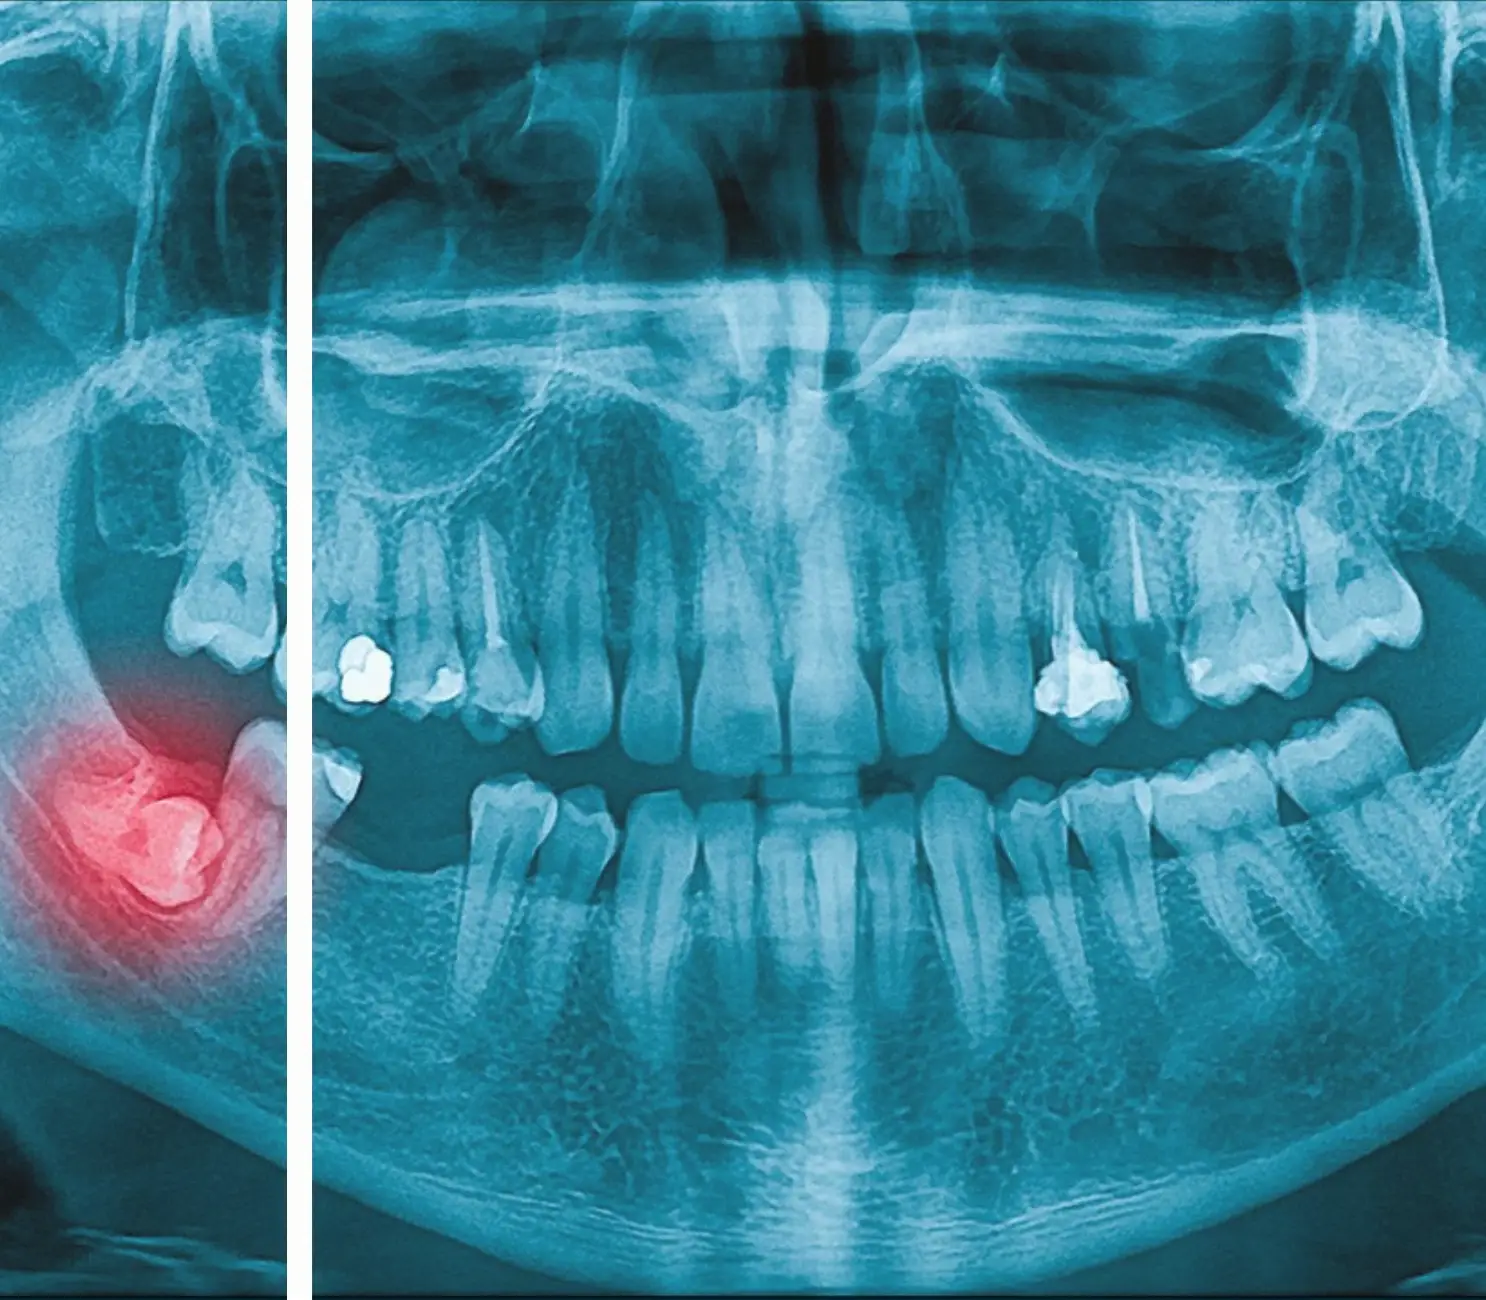

Gömülü diş çekiminde doğru planlama büyük önem taşır. Dişin çene kemiğindeki konumu, köklerin şekli, sinir hattına yakınlığı ve komşu dişlerle ilişkisi dikkatle incelenmeden işlem planlanmamalıdır. Bu sayede daha kontrollü ve öngörülebilir bir cerrahi süreç hedeflenir.

- Gömülü dişin pozisyonu detaylı incelenir.

- Gerekli durumlarda panoramik röntgen veya ileri görüntüleme değerlendirilir.

- Çevre anatomik yapılar ve sinir hattı göz önünde bulundurulur.